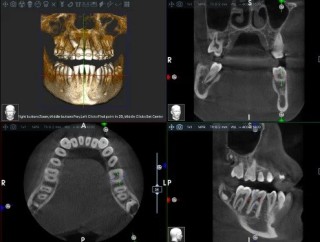

X-Mind Optima Ceph 3D wyznacza nowy standard dla gabinetów. Zastosowane w nim innowacyjne oprogramowanie RealGuide™ 5.4, wspierane sztuczną inteligencją, znacząco usprawnia zaawansowane procedury diagnostyczne i implantologiczne. Inteligentne algorytmy automatyzują kluczowe etapy pracy, co ułatwia planowanie i przeprowadzanie skomplikowanych zabiegów. Urządzenie stanowi niezastąpione wsparcie w segmentacji zębów, wyznaczaniu linii CPR, analizie przebiegu nerwów oraz precyzyjnym pozycjonowaniu implantów.

Oprogramowanie Acteon Imaging Suite oferuje pełne zarządzanie danymi diagnostycznymi, umożliwiając płynną integrację tomografu CBCT X-Mind Optima 3D z pozostałym sprzętem w gabinecie. Obsługa standardu DICOM ułatwia archiwizację i wymianę obrazów, a szeroka kompatybilność z systemami radiologicznymi usprawnia współpracę w środowisku wielospecjalistycznym. Rozbudowane funkcje raportowania pozwalają na szybkie tworzenie dokumentacji, dokładną analizę przypadków oraz wygodne udostępnianie wyników w formie cyfrowej.